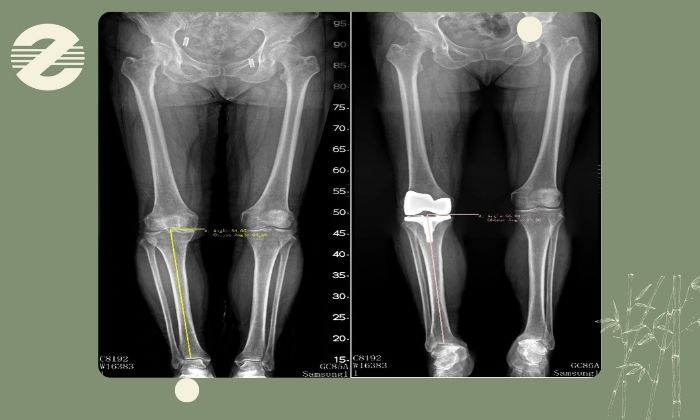

رادیوگرافی الایمنت ویو چیست؟

این روش یکی از روش های تشخیص اساسی پزشکان ارتوپد برای بررسی زاویه مکانیکی و آناتومیک اندامهای تحتانی به شمار میرود. در واقع با الایمنت ویو مشخص میشود که استخوانهای ران، ساق و مچ در محور طبیعی خود قرار دارند یا دچار انحراف هستند چرا که همین تغییر زاویهها علت بسیاری از مشکلات درد زانو، ساییدگی مفصل و ناهنجاریهای حرکتی است.